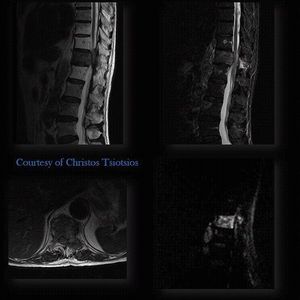

Figure shows a patient with vertebral metastasis (Th12). Multiparametric imaging (based on anatomical and functional imaging) can solve the clinical question without the need of Gadolinium. SS-EPI DWI is not ideal for spine imaging due to issues of susceptibility artifacts and distortions, but it's possible with proper optimization of the sequence.